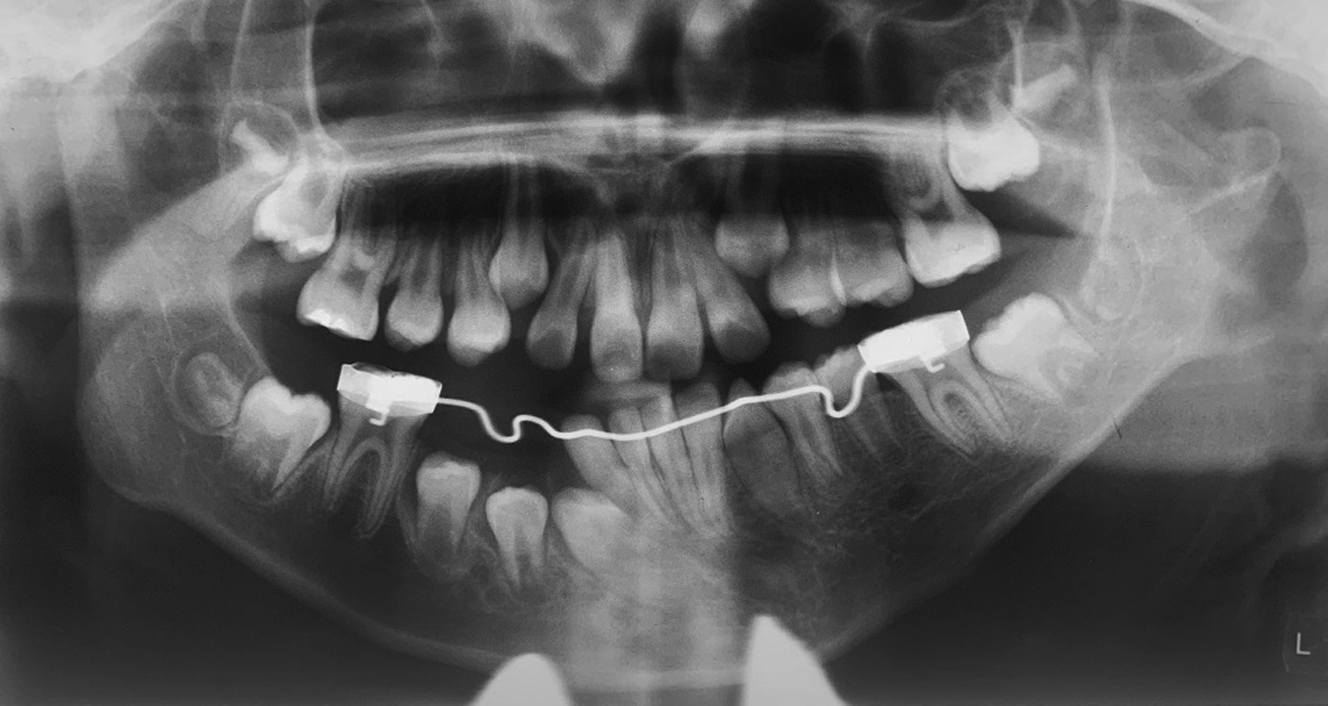

There may be interferences unaccounted for or unpredicted movement during activation requiring intervention to mold the generate during the consolidation phase. The consolidation period usually spans 8 weeks after activation is deemed complete. During consolidation and postoperatively, the occlusion must be idealized and the patient should be closely followed by the orthodontist. Often there is significant occlusal adjustment required to establish a stable bite after activation is complete. Note that the actual vector observed often differs from the one planned presurgically, and can be affected by the biomechanics of the individual device, the differences in individual mandibular anatomy, neuromuscular effects, and external force. Fixed braces can be used for patients with adult dentition, whereas bonded splints with hooks may be necessary in patients with short clinical crowns or multiple missing teeth. Temporary anchorage devices (TADs) or intermaxillary fixation screws are useful in all patients for the application of bone-borne forces ( Figs. 5 and 6 ). The forces are ideally distributed over the basilar portion of the jaws to avoid extrusion of individual teeth, and TADs achieve this effectively. Interdental orthodontic elastics used in conjunction with any of the appliances mentioned earlier can assist in molding the bony generate during both the activation and consolidation phases. Heavy elastic forces should be applied immediately during the consolidation phase because they are deemed ineffective at idealizing the alveolus once the bone has consolidated. It is recommended that the distractors remain while elastic forces are being used during the full consolidation period; if removed too early, there can be bending of the bony generate and buckling from the weakness. Interestingly, orthopedic and orthodontic forces are more efficient and effective during these healing phases, likely because of increased bone metabolism after surgical trauma. This finding results in a window of opportunity during which time orthodontic visits should be frequent in order to accomplish treatment goals.